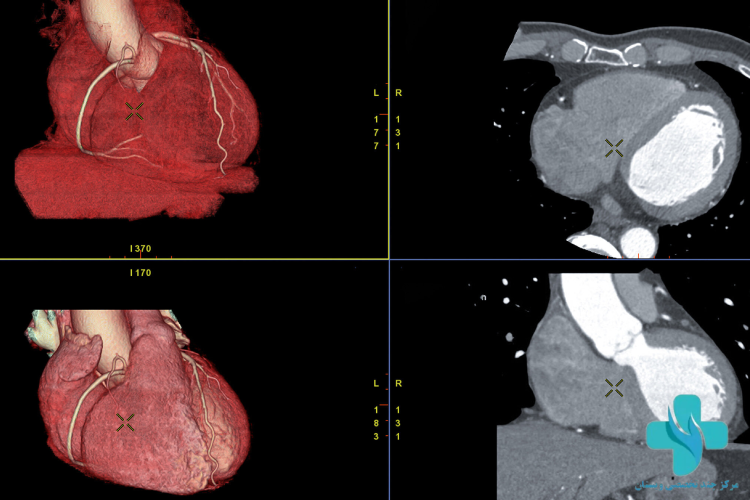

سی تی آنژیوگرافی قلب (CT Angiography) یک روش تصویربرداری غیرتهاجمی برای بررسی عروق کرونری قلب است. در این روش، با استفاده از دستگاه سی تی اسکن و تزریق ماده حاجب، تصاویری دقیق و واضح از رگهای قلب به دست میآید. این روش برای افرادی توصیه میشود که علائم بیماریهای قلبی دارند مانند درد قفسه سینه، تنگی نفس یا سابقه خانوادگی مشکلات قلبی.

مزیت اصلی سی تی آنژیو نسبت به آنژیوگرافی سنتی، غیرتهاجمی بودن، سرعت بالا و نداشتن نیاز به بستری است. این تست میتواند انسداد، تنگی یا گرفتگی عروق کرونری را در مراحل اولیه شناسایی کند و در تصمیمگیریهای پزشکی نقش مهمی دارد.

سی تی آنژیو قلب یک روش پیشرفته و غیرتهاجمی برای بررسی دقیق عروق کرونر است که با استفاده از اشعه ایکس و ماده حاجب انجام میشود. این روش میتواند انسداد، تنگی یا ناهنجاریهای عروق قلب را بدون نیاز به عمل جراحی نشان دهد. در ادامه مراحل انجام آن را بهصورت گامبهگام مرور میکنیم:

- دستگاه سی تی اسکن با چرخش دور قفسه سینه، تصاویری دقیق از قلب و عروق تهیه میکند.

- بیمار باید در حین تصویربرداری برای چند ثانیه نفس خود را نگه دارد تا تصاویر واضحتر باشند.

- کل فرآیند تصویربرداری معمولاً بین ۱۰ تا ۲۰ دقیقه طول میکشد.

نکته مهم: انجام این تصویربرداری در مراکز تخصصی مانند کلینیک قلب ویستان که مجهز به دستگاههای مولتیاسلایس و تیم پزشکی مجرب است، موجب افزایش دقت تشخیص و کاهش احتمال خطا میشود.

بیمارستان جم تهران بهعنوان یکی از مراکز خصوصی معتبر در حوزه خدمات تخصصی قلب و تصویربرداری پزشکی، سی تی آنژیو قلب را با استفاده از دستگاههای پیشرفته مولتیاسلایس و تیم پزشکی مجرب انجام میدهد. این روش تصویربرداری پیشرفته، امکان بررسی دقیق عروق کرونری قلب را بدون نیاز به جراحی فراهم میکند و در تشخیص تنگی یا انسداد عروق نقش بسیار مؤثری دارد.